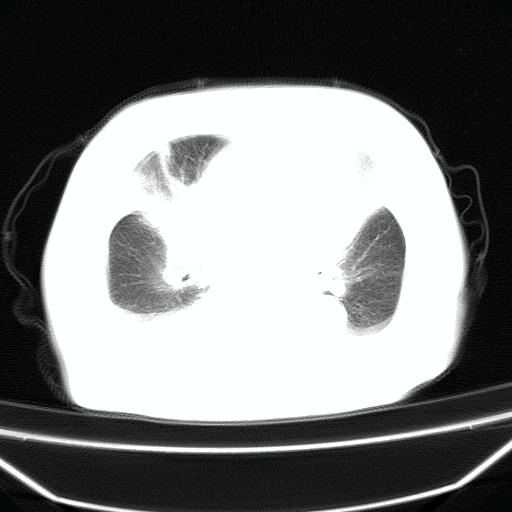

以下是引用jiangjing在2008-4-20 10:43:00的发言:[br]结合病史支持 冠心病[冠状动脉钙化],心功能不全,肺淤血、肺水肿,双侧胸腔与斜裂积液

以下是引用liuyue在2008-4-19 22:25:00的发言:[br]先考虑:1.心衰伴肺水肿、双侧胸腔积液、叶间积液、双下肺不完全性肺不张; [br] 2.冠状动脉粥样硬化。